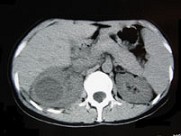

- 多项选择题女,33岁, 右胁腹痛7天,尿检可见大量的脓细胞, CT平扫+增强如图所示,下列说法正确的是 ( )

A、右肾体积增大,其内可见类圆形低密度病灶

B、增强扫描可见该病灶不均匀强化,其内有无强化的坏死灶

C、右肾病灶边界模糊不清

D、考虑为右肾囊肿合并感染

E、考虑为右肾脓肿